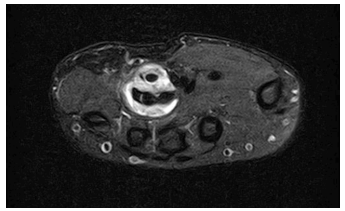

Herein is reported the case of a 15-year-old female adolescent followed at the Orthopedic Outpatient Clinic due to chronic hand pain following trauma to the right hypothenar region and flexor carpi ulnaris one year before. She was admitted to the Pediatric Emergency Department (PED) at the time of trauma and conservatively managed. In the following months, the girl returned to PED with similar pain complaints. X-ray imaging revealed no signs of additional hand injury, but the girl was referred to the outpatient clinic for further study. Magnetic resonance imaging (MRI) showed tenosynovitis of the common flexors of the right hand and rupture of the superficial flexor tendon of the small finger (Figures 1 and 2). The patient initially underwent physical therapy with no significant relief. She was ultimately proposed for surgery and underwent pulley release and synovectomy of the flexor tendons in a private clinical facility, being lost to follow-up. Five months after surgery, she returned to PED with persistent right hand pain. She shared the histopathological report previously performed, which evidenced severe chronic synovitis of the flexor tendons of the right wrist and caseous central-necrotic granulomas, highly suggestive of tuberculous disease. Acid-Fast stain was negative. Personal history was again carefully retrieved, but no known contacts with active or past disease or recent traveling outside the country were identified. The etiological study was continued, with no relevant findings in chest radiography but positive results in both Tuberculin Skin Test and Interferon-Gamma Releasing Assay. At this point, tuberculous involvement of the flexor tendons of the right hand with concurrent chronic synovitis was assumed. The patient complied with 12-month anti-tuberculous chemotherapy with isoniazid, rifampicin, pyrazinamide, and ethambutol for two months, followed by isoniazid and rifampicin for ten months. Five years after the initial hand trauma, the patient remained under clinical surveillance, with persistent chronic pain and intermittent paraesthesia of the right hand, although less severe than before treatment. Additionally, functional limitation of flexion of the 4th and 5th fingers of the right hand persisted as a chronic synovitis complication (Figure 3).

Figure 2 Magnetic resonance imaging of the wrist. Axial T2 fat saturation image showing hyperintense signal surrounding inflammation of the flexor digitorum superficialis and profundus of the 4th finger.